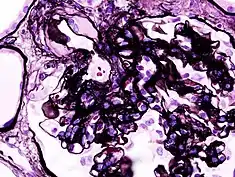

Microscopic image of diabetic glomerulosclerosis, the main cause of nephrotic syndrome in adults.

Diabetic glomerulonephritis in a person with nephrotic syndrome.

Secondary causes of nephrotic syndrome have the same histologic patterns as the primary causes, though they may exhibit some differences suggesting a secondary cause, such as inclusion bodies.[24] They are usually described by the underlying cause, such as: